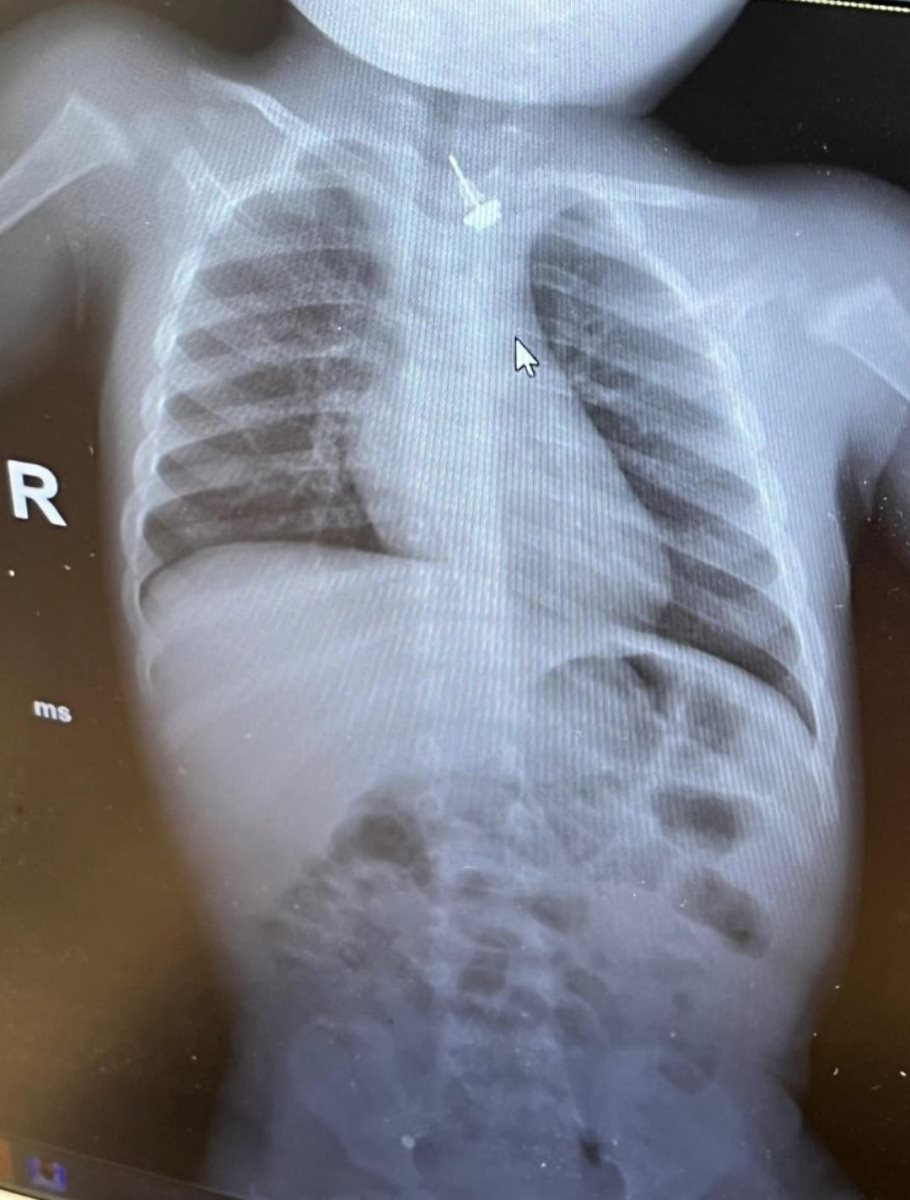

כשהגיעו אל המרכז, הצוות קיבל אותם במהירות לקבלת טיפול רפואי מידי. ד"ר קאסם נמר, מומחה לרפואה דחופה במאוחדת ורופא חדר מיון בהדסה עין כרם, בדק את התינוק. "בצילום הרנטגן ראינו באופן ברור כי העגיל נמצא במקום מסוכן, בסמוך מאוד לקנה הנשימה ועם חשש ממשי לחסימה של נתיבי האוויר".